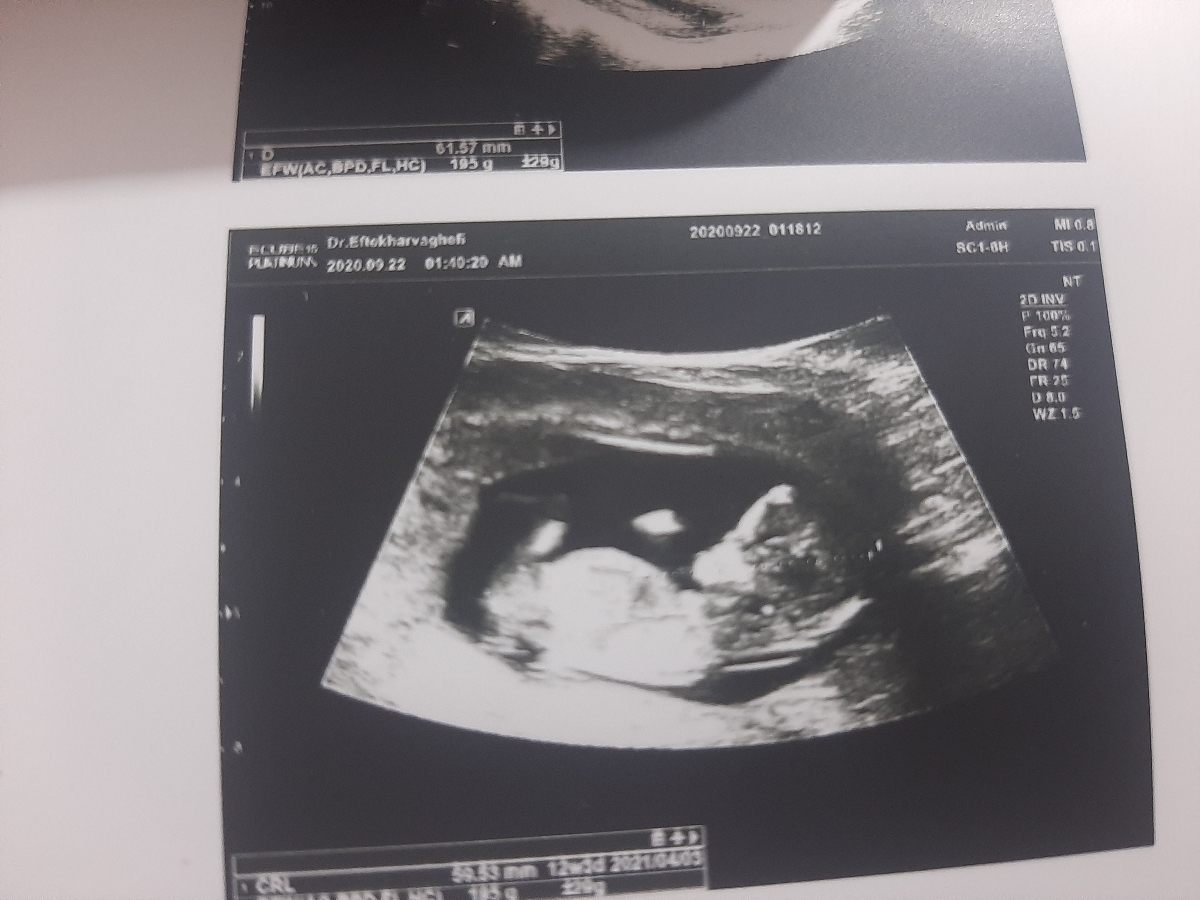

سلام بچه ها امروز رفتم ان تی دکتر گفت همه چیزش خوبه فقط بهم نگفت چیه حدس بزنین چیه

مثانه ام خیلی پر بود دکترم گفت زیاد شد به دلیل پر بودن مثانه ۶۱ بود

خدا حفظش کنه احساس میکنم پسره

سلام عزیزم دختره

سلام به نظر من دختره

سلام ضایع پسره راست کرده😜🤣🤣

پسر .